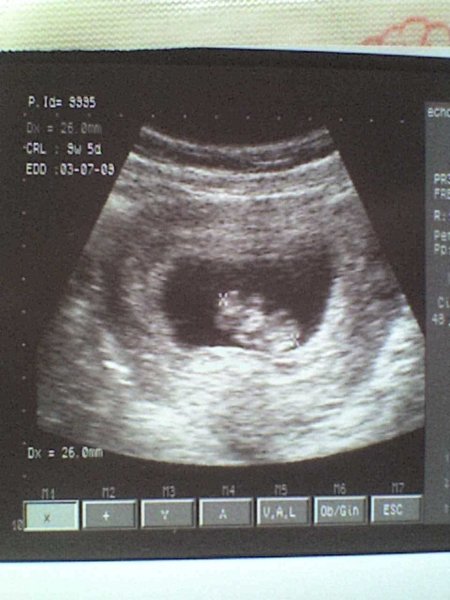

jobbra az okos feje, keze-lába égnek áll,baloldalt a formás popsija, hátán fekszik. 26 mm, 9+5 volt dec3-án.

szerintetek sakkozni vagy úszni járjon a testfelépítéséből adódóan? :)

és Nati: ez csak egy darab baba:))) Zsófién keresd majd a sokat!:)